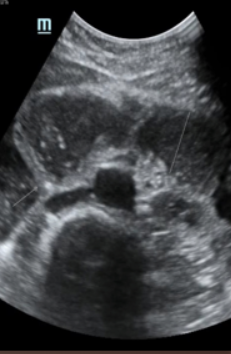

Fluid filled cecum